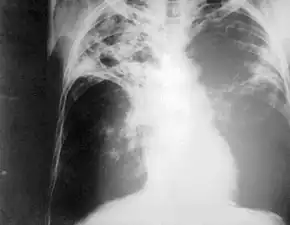

Chest radiography showing advanced bilateral pulmonary tuberculosis. Source: CDC

Chest photofluorography, or abreugraphy (better known as mass miniature radiography in the UK and miniature chest radiograph in the US), is a photofluorography technique for mass screening for tuberculosis using a miniature (50 to 100 mm) photograph of the screen of an X-ray fluoroscopy of the thorax, first developed in 1936.